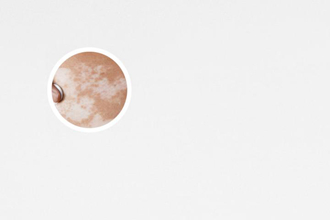

白癜風(fēng)是一種色素性皮膚病,臨床表現(xiàn)為皮膚白斑,白斑可出現(xiàn)在身體任何部位,大小不一,形狀多樣。白斑顏色呈乳白色、瓷白色、淡白色或云白色,邊緣清晰,表面光滑,無(wú)皮疹及鱗屑,白斑部位皮膚一般無(wú)顯然感覺(jué)異常,但部分患者可能會(huì)有輕微的瘙癢或灼熱感。白癜風(fēng)不是癌癥,不會(huì)危及生命,但會(huì)影響患者的外觀,導(dǎo)致心理負(fù)擔(dān),甚至影響患者的社交活動(dòng)。